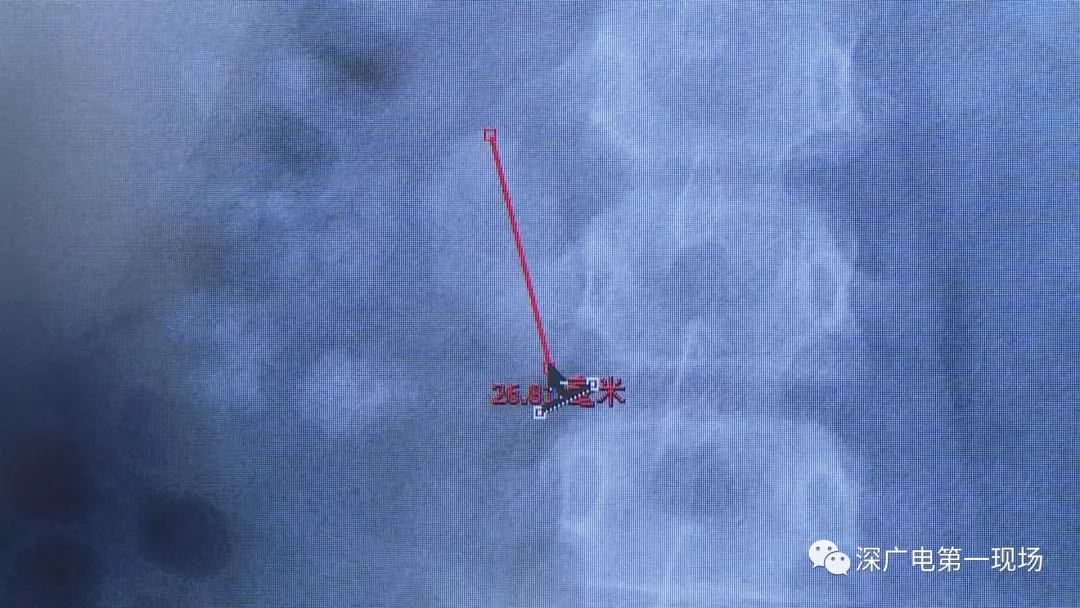

在X光圖像下,醫(yī)生發(fā)現(xiàn)小軒的雙側(cè)腎臟都內(nèi)藏乾坤,密密麻麻的分布著大小不等的結(jié)石。

小軒這種情況,其中,最大的結(jié)石長(zhǎng)約2.7厘米,寬約1.7厘米,體積堪比鵪鶉蛋,不但造成了尿路堵塞,還導(dǎo)致了右腎中度積水。